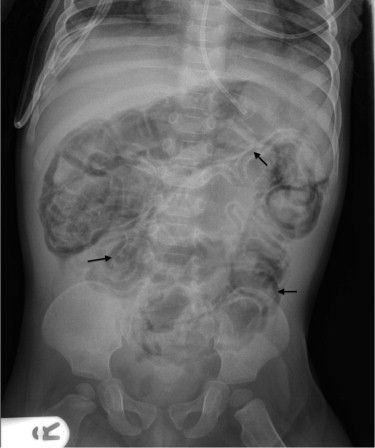

Pneumatosis intestinalis refers to gas in the wall of the gut. The presence of air in the gut wall may be indicative of benign or dangerous conditions. If associated with ischemia, it is considered dangerous. Additionally, in children, the condition may be indicative of necrotizing enterocolitis. Reference: https://emedicine.medscape.com/article/371955-overview#a1 Image via: https://www.jpeds.com/article/S0022-3476(14)00444-2/fulltext